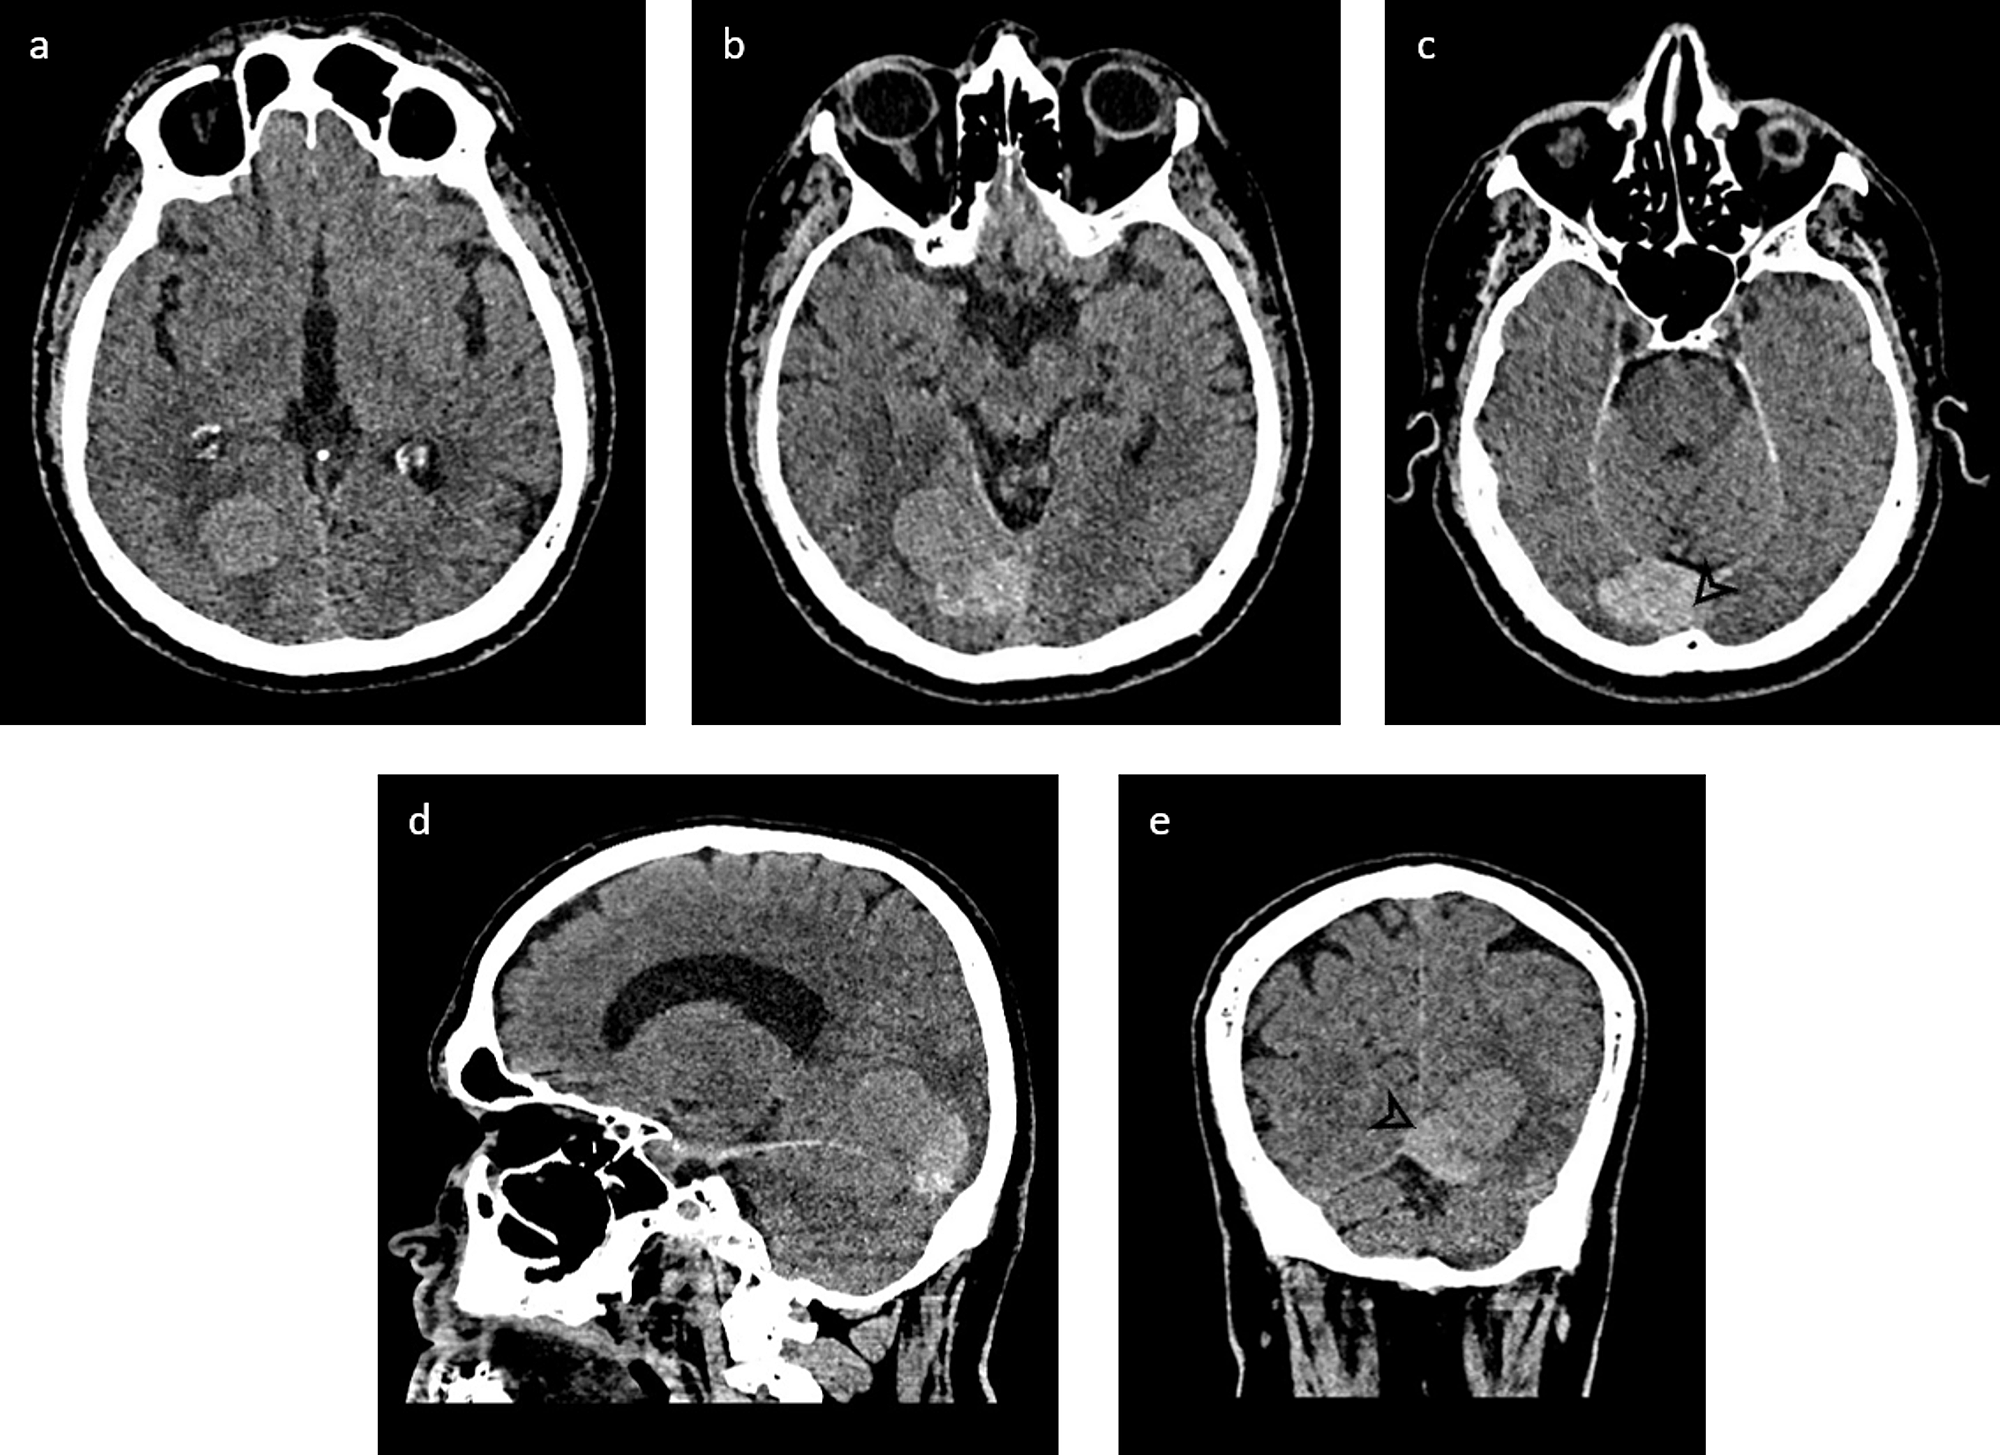

From radiopaedia.org

Solitary fibrous tumor (hemangiopericytoma) Image Hemangiopericytoma Radiosurgery The authors report a large multicenter study, through the international gamma knife research foundation (igkrf), reviewing. Although postoperative adjuvant radiotherapy is. Stereotactic radiosurgery of hemangiopericytomas can result in increased tumor control and should be considered as a treatment. Intracranial hemangiopericytoma is a rare disease and surgery is the mainstay treatment. Radiosurgery is a reasonable treatment option for recurrent hemangiopericytomas. Hemangiopericytoma,. Hemangiopericytoma Radiosurgery.